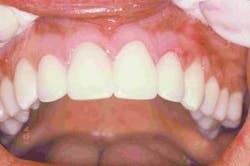

Delivering superior cosmetic and restorative dentistry requires more than just knowledge of sound biological principles, mechanical properties, proper techniques, and restorative materials. One must have a critical eye and judgment for assessing detail, and master the communication skills to consider the patient's needs in conjunction with applying your expertise during treatment planning and execution. It is essential to take advantage of the technological advances available every step of the way, from digital technology to shade-matching devices to dental adhesives to new porcelains. By aiming to go beyond the task of just merely improving misaligned, discolored teeth, we were able to create a truly stunning, spectacular smile (Figures 21, 22).